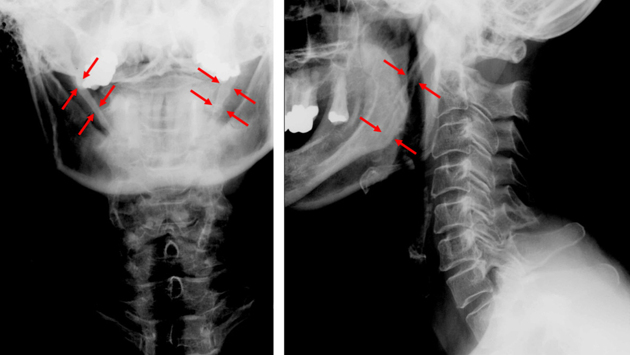

На КТ было обнаружено аномальное удлинение шиловидных отростков — костных выступов у основания черепа. В норме их длина не превышает 3 сантиметров. А у ребенка они выросли до 6 сантиметров с каждой стороны. Это заболевание обычно встречается только у взрослых пациентов в возрасте 30–50 лет. Отростки удлиняются за счет окостенения шилоподъязычной связки. Точные причины этого процесса неизвестны. Но иногда эта связка может начать накапливать кальций на фоне множественных инфекционных заболеваний ротоглотки.